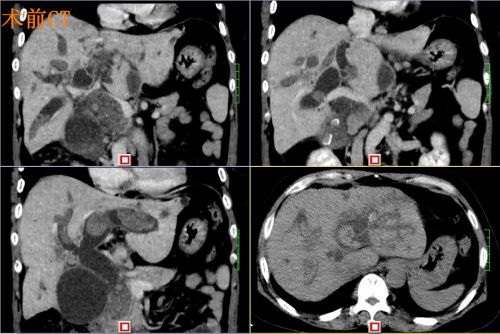

术前ct

尹女士肝内胆管多发结石,结石遍布肝脏所有胆管,要将结石全部清除,手术难度很大。首席专家吴金术教授和肝胆捷克论坛 院长蒋波教授的指导下,2月20日,尹新民教授团队为尹女士实施腹腔镜下胆囊切除、胆总管切开取石、左肝管劈开取石、S5胆管劈开取石、右肝后叶及尾叶取石、S8胆管钬激光碎石、肝方叶切除、左肝外叶切除、肝门胆管整形、胆总管离断一胆肠内引流术。

患者肝内布满结石,又有胆道畸形和狭窄,手术实施非常困难。为了把结石清除干净,尹新民教授团队遵循吴金术教授20字肝胆管结石治疗方针——“取尽结石,解除狭窄,切除病肝,矫正畸形,通畅引流”,用尽十八般武器,坚持不懈,奋战14个小时,最终把结石清除干净,术中出血不足200毫升。